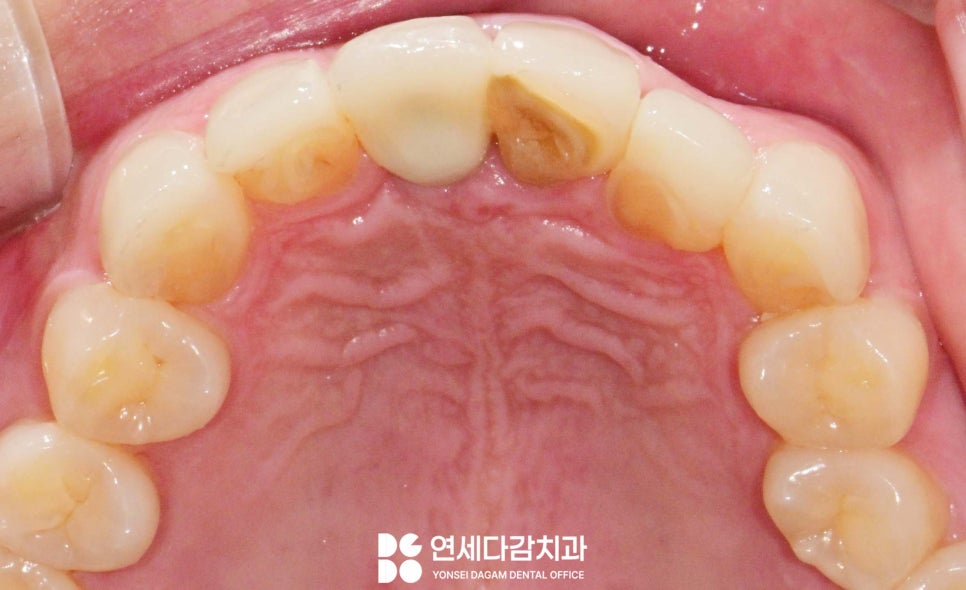

예를들어 일부 치아의 경우

거여동 치과 에서 표시한 것 처럼

잇몸이 치관을 많이 덮고 있어,

웃을 때 치아가 짧아 보이거나

잇몸이 과도하게 드러나는 상태를 고려하여

치은 성형술을 동반하기도 합니다.

또한 정중앙에 있는 앞니가 앞으로

돌출되어 있는 형태라면

전체적인 인상에 부정적인 영향을 줄 수 있어

돌출도를 감소할 수 있도록

치료 계획을 세워야 됩니다.

치은 성형술

보철 치료를 진행하기 앞서

과하게 덮고 있던 잇몸의 형태를

예쁘게 만들어야

더 나은 심미적 개선을 얻을 수 있습니다.

치은 성형술이란 치아 주변

과다 성장하거나 불규칙한 모양 및

잔여 잇몸 조직(치은)의 형태를

심미적 및 기능적 개선 목적으로

다듬는 과정입니다.

치관이 짧아 보이는

특정 치아에만 시행하여

전체적인 치아 비율의 균형을 맞춥니다.